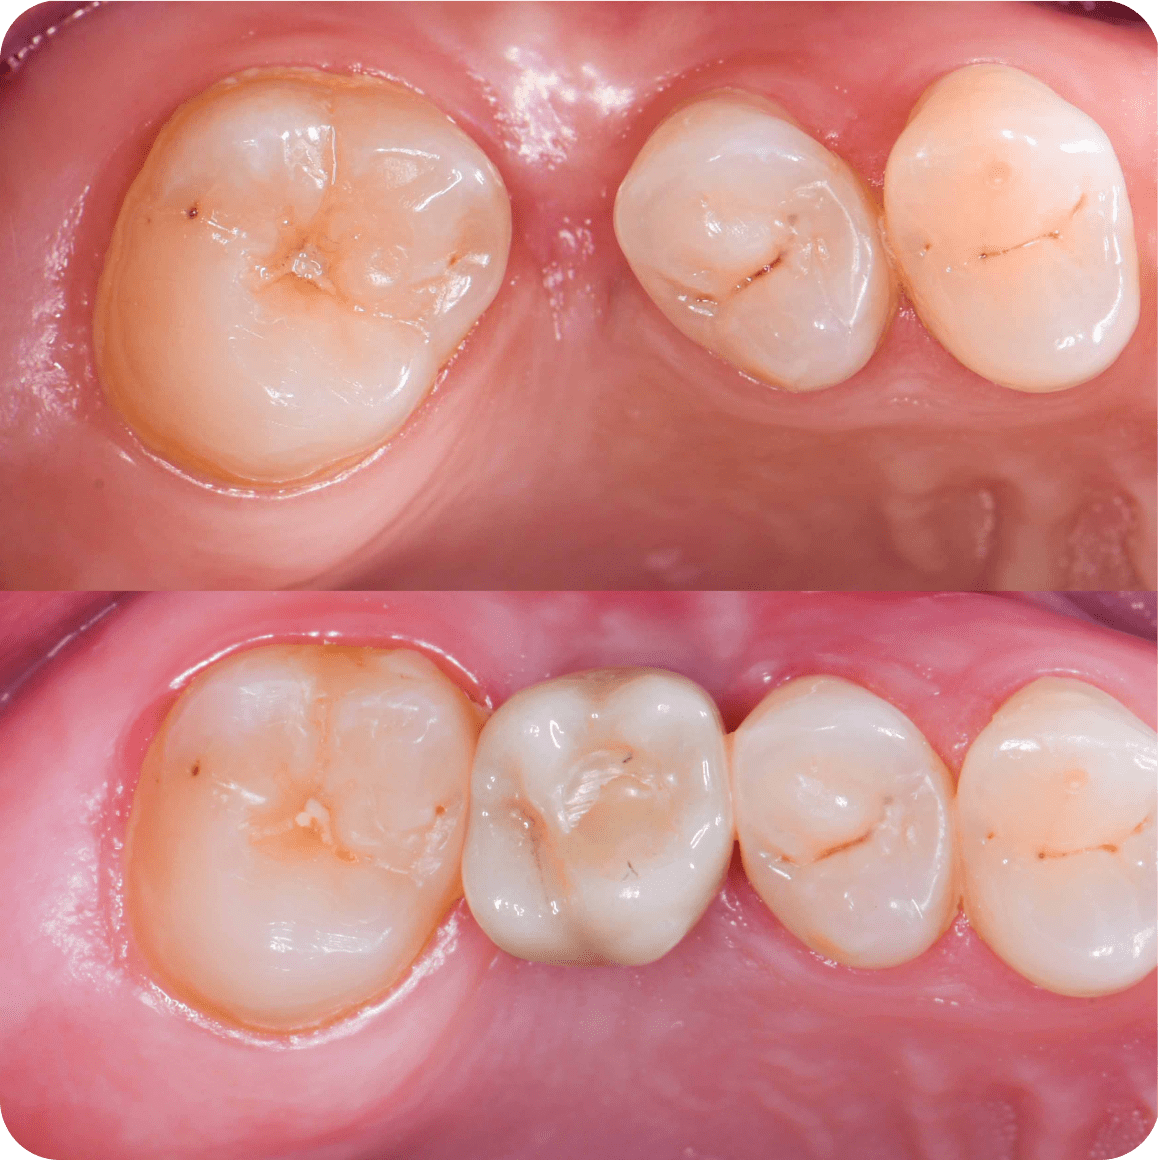

Установка коронки

Через 3-4 месяца пациенту сканируют имплант для изготовления постоянной керамической коронки

7-14 дней коронка на импланте изготавливается в зуботехнической лаборатории

C момента операции, пациент получает готовый зуб через 3-6 месяцев